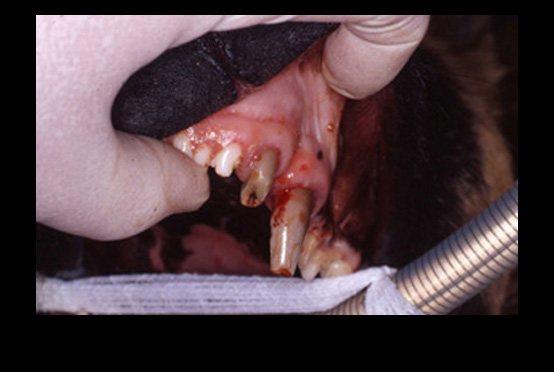

NOTICE: Veterinarians have used spring-loaded mouth "gags" in cats and dogs for many years. However, the spring-loaded devices are no longer recommended. A study published in THE VETERINARY JOURNAL (2014) showed that the spring-loaded "gags" generating constant force contributes to bulging of the soft tissues between the mandible and the tympanic bulla in cats. This force leads to the compression of the maxillary arteries as they course through the osseous structures. In cats the maxillary arteries are the main source of blood supply to the retinae and brain.

Reduction of the blood flow can result in temporary or permanent blindness and neurologic abnormalities. Spring-loaded "gags" constant force can also cause jaw muscle strain and injury to the temporomandibular joints.

It is recommended to use "static" mouth props such as the WEDGE. Be sure to not open the jaw to its maximum to avoid muscle strain and temporomandibular joint injury.